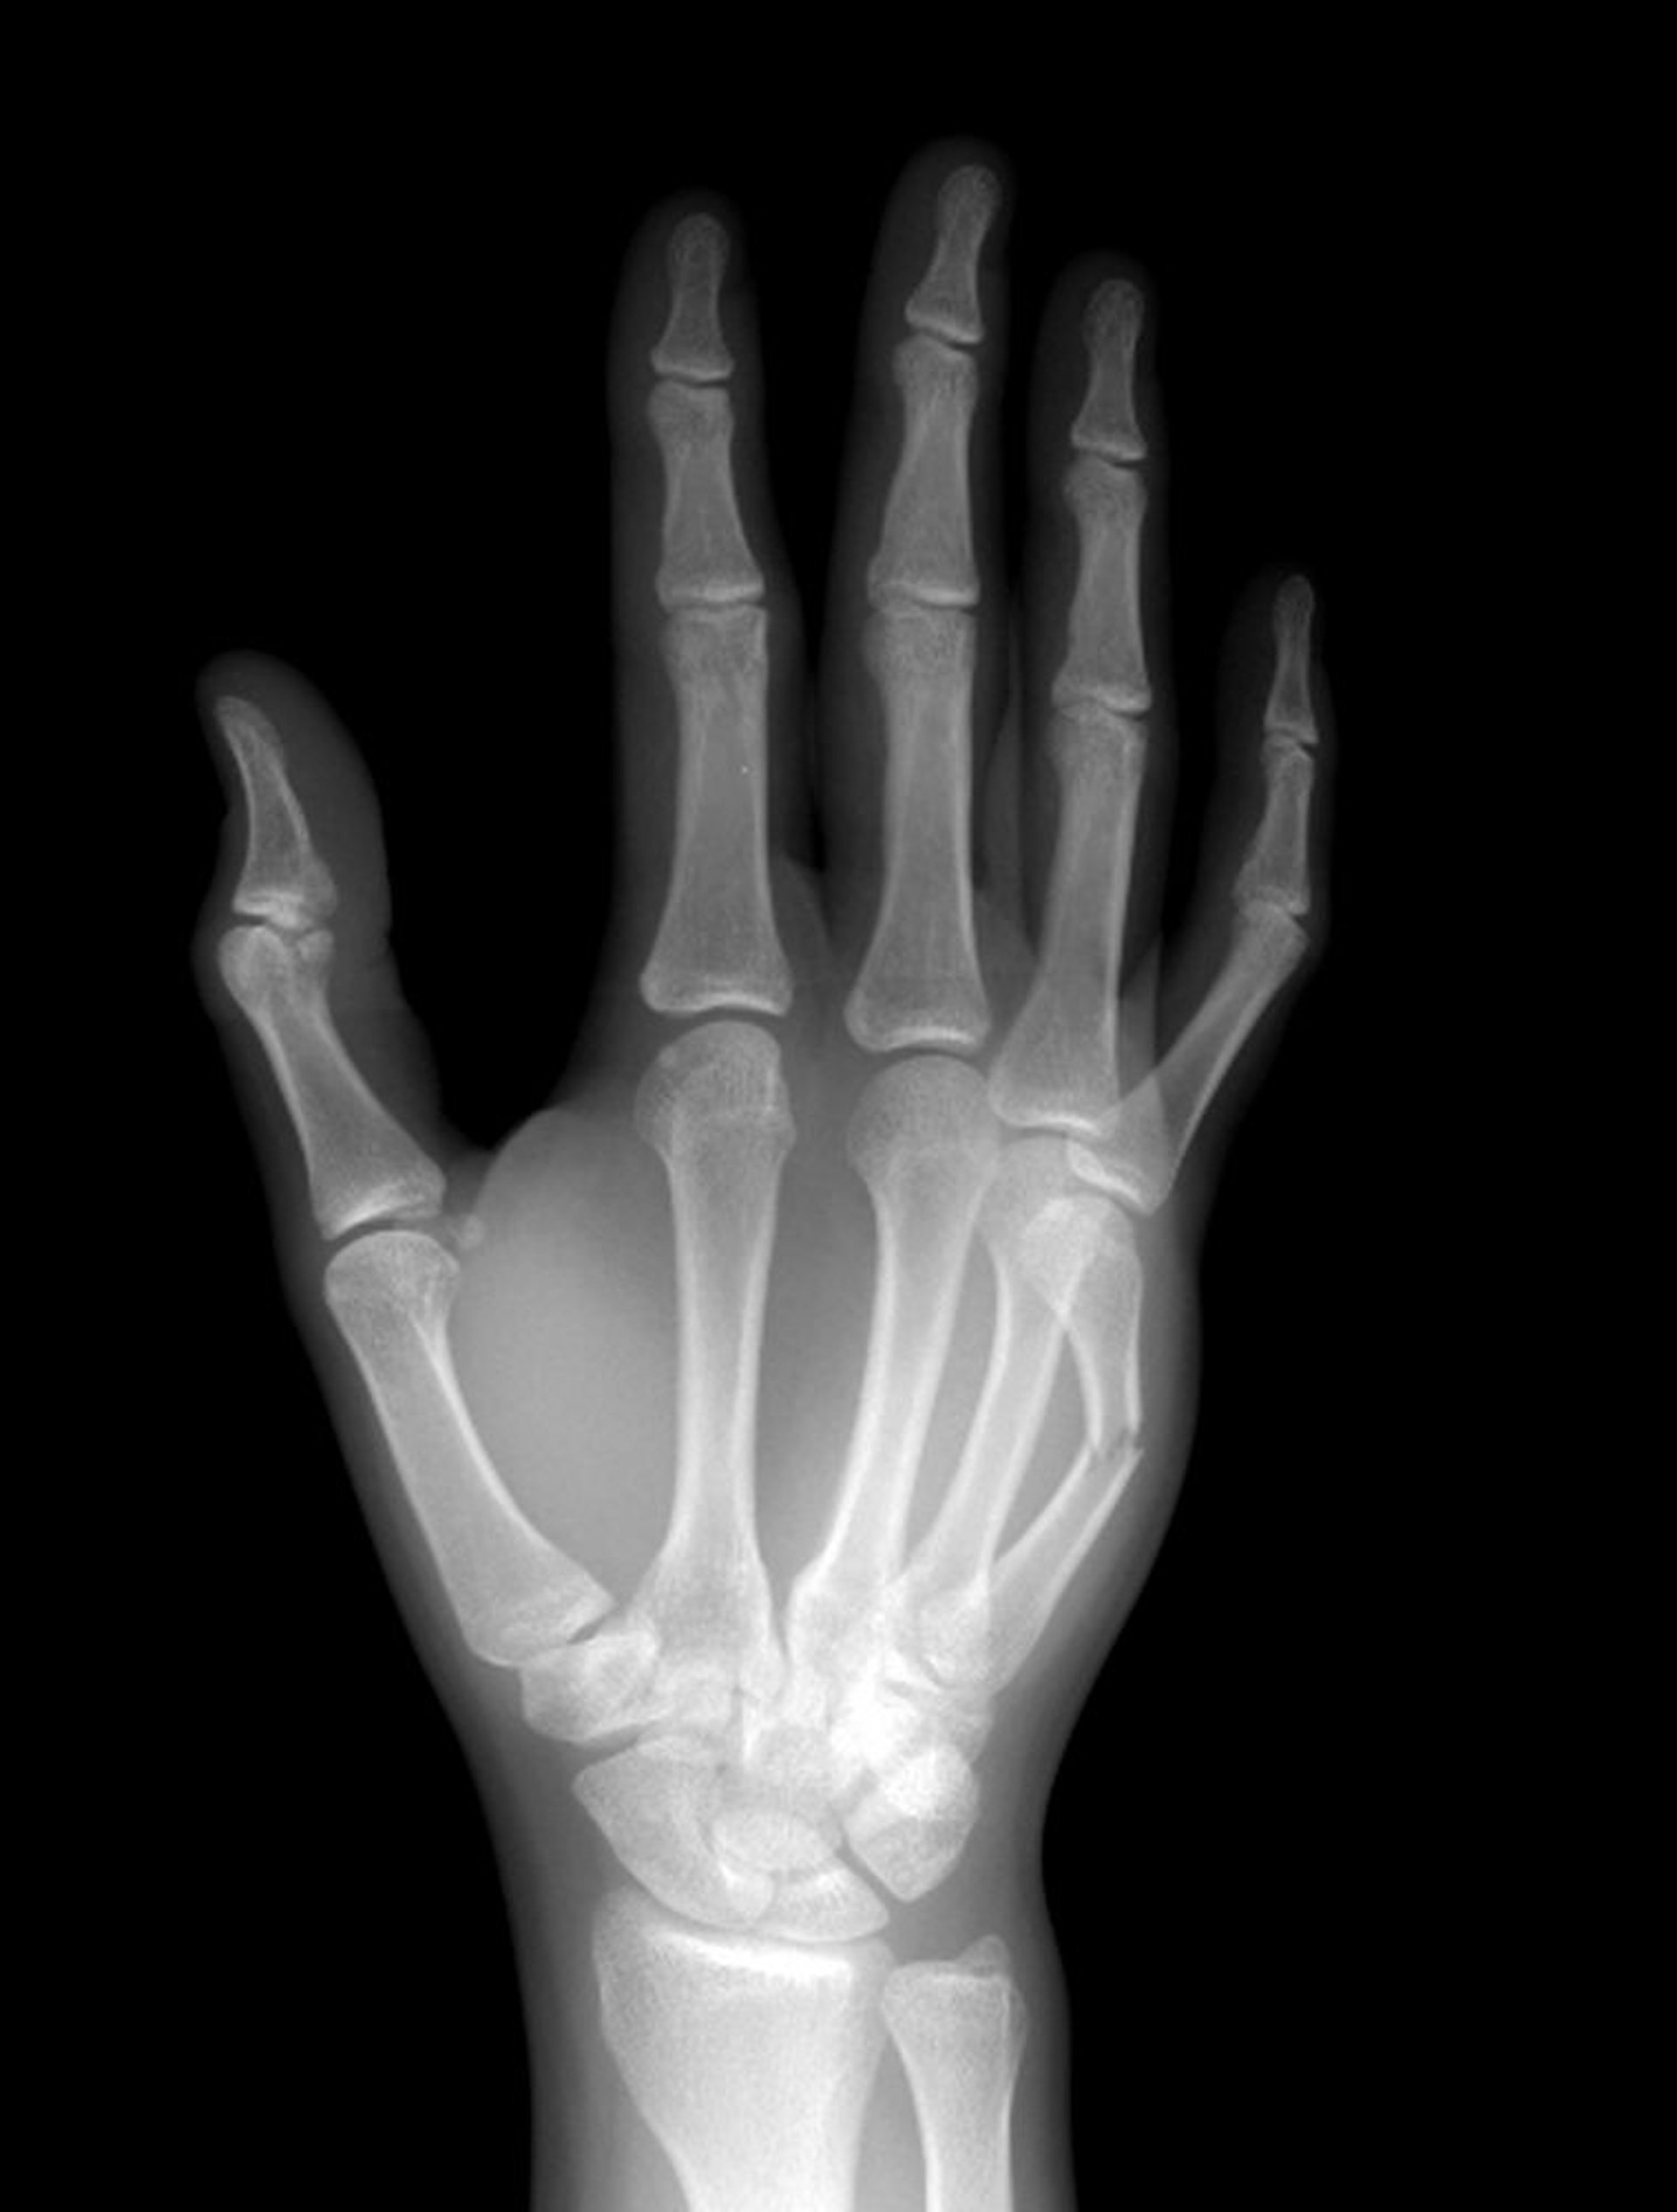

Karpometakarpalfrakturen

Der 5. Mittelhandknochen ist in der Mitte des Schafts gebrochen.